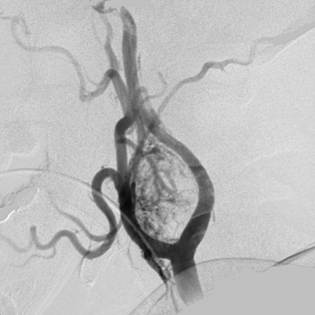

Q.5

Clinical Question:

Following a building collapse, a male patient was brought to the emergency department with a copious amount of debris in the mouth, making endotracheal intubation impossible. The emergency procedure shown in the image was performed. Which of the following statements regarding this procedure is true?

Options:

- It is used for effective ventilation for up to 6 hours

- It is used to measure central venous pressure

- It should be followed by a tracheostomy

- The work of breathing is more than with bag-and-mask ventilation

Correct Answer: C) It should be followed by a tracheostomy